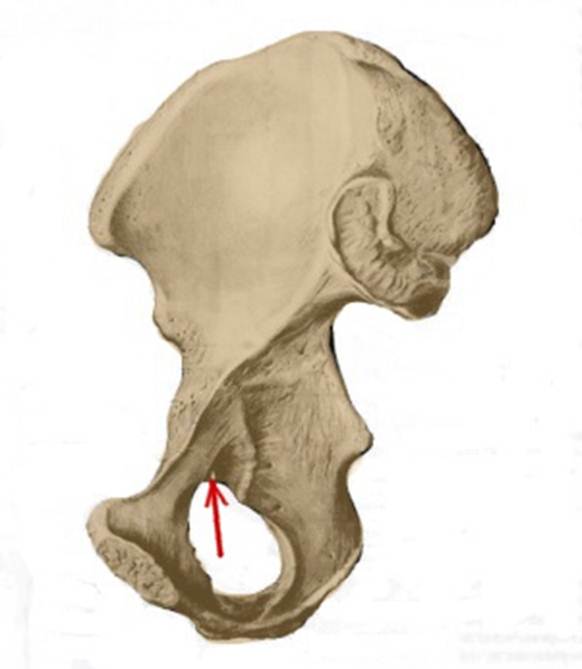

S: Стрелка указывает на os pubis (латинский язык).

S: Стрелка указывает на os ischii (латинский язык).

S: Стрелка указывает на ramus superior ossis pubis

S: Стрелка указывает на ramus inferior ossis pubis

S: Стрелка указывает на ramus ossis ischii

S: Стрелка указывает на tuber ischiadicum (латинский язык).

S: Стрелка указывает на foramen obturatum (латинский язык).

S: Стрелка указывает на tuberculum pubicum

S: Стрелка указывает на incisura ischiadica minor

S: Стрелка указывает на incisura acetabuli

S: Стрелка указывает на sulcus obturatorius (латинский язык).